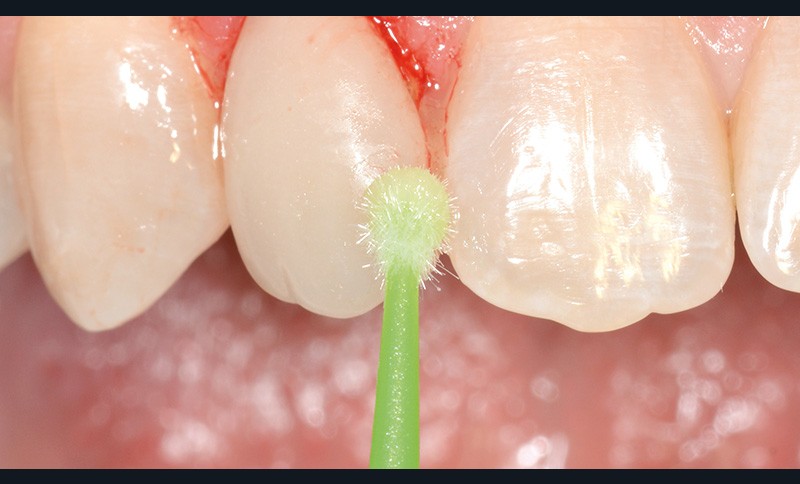

bibli/1.2.11.jpgUne brosse et une ponce sont appliquées afin d’éliminer tous les résidus extrinsèques.

bibli/1.11.jpgNettoyage, surfaçage et polissage parfait des surfaces dures.

bibli/1.2.11.jpgUne brosse et une ponce sont appliquées afin d’éliminer tous les résidus extrinsèques.